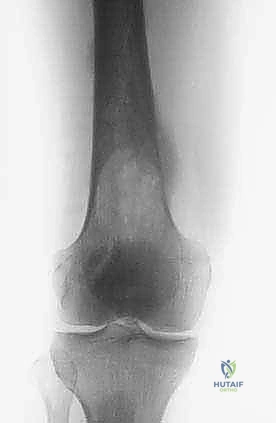

- الأشعة السينية العادية (X-rays): هي الخطوة الأولى دائماً. تظهر النقائل الحالة للعظم كبقع داكنة (ثقوب) في العظم، بينما تظهر النقائل البانية كبقع بيضاء كثيفة. الأشعة السينية ضرورية لتقييم خطر الكسر.

- التصوير المقطعي المحوسب (CT Scan): يقدم تفاصيل ثلاثية الأبعاد لا مثيل لها لجودة القشرة العظمية المتبقية. يساعد الجراح في التخطيط لحجم المسامير أو الصفائح المطلوبة، وتقييم مدى تدمير العظم.